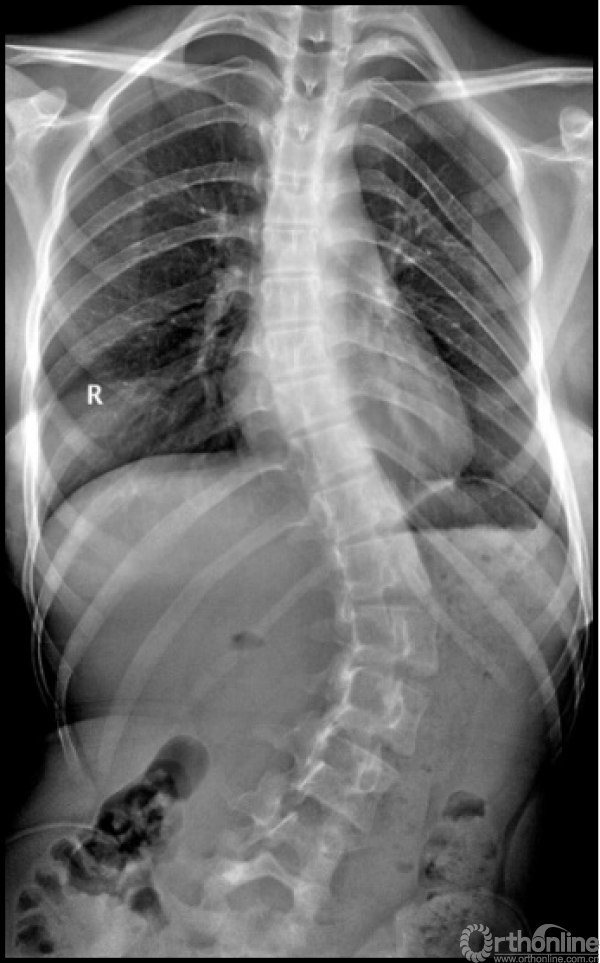

图7. Lenke 5C型AIS患者前路术后矫正效果满意,随访23年无明显进展